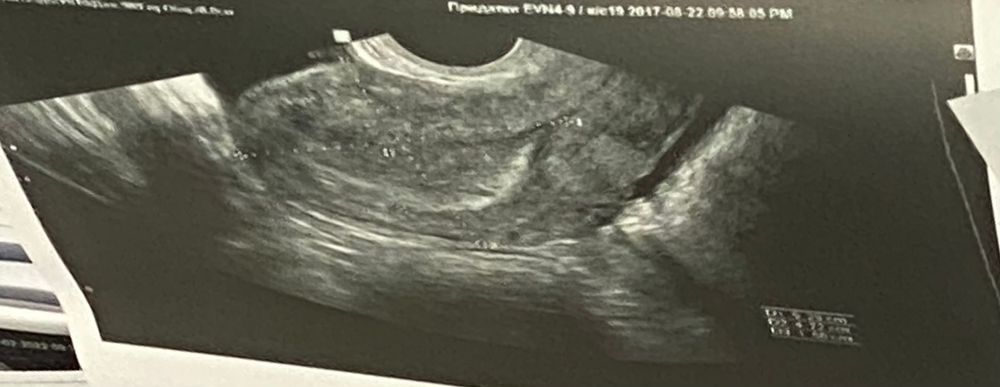

не видно плодного яйца

здравствуйте, была на узи, матка увеличена, тесты на беременность положительные, но нет плодного яйца, я не беременна? или это из-за маленького срока?